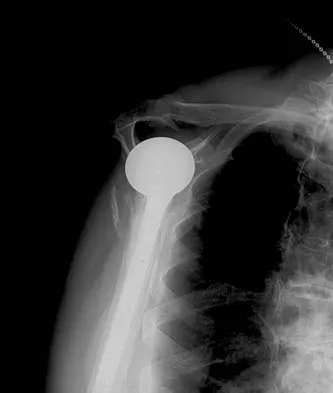

Which of the following findings is seen in the chest radiograph shown in Figure 13?

Orthopaedic surgeons are often responsible for interpreting radiographs of general examinations such as the chest radiograph shown. For accurate interpretation, it is important to systematically review all of the information available on the radiograph. Using this approach, the fracture of the left proximal humerus is readily recognized. Linear air soft-tissue density at the lung periphery would suggest a pneumothorax, but this finding is not shown on the radiograph. The upper thoracic spine is well aligned. The sternoclavicular and distal clavicles are normal.